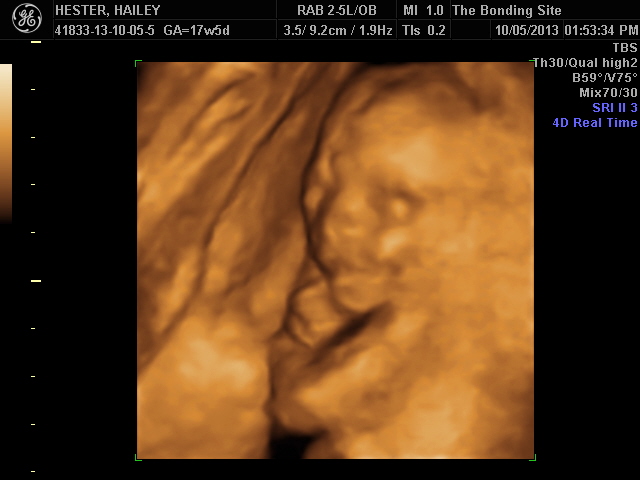

This is 16 weeks when we found out she is a she! Sorry, it's a little blurry. Hopefully I'll have another 3D ultrasound in a month or so to get some better pictures!